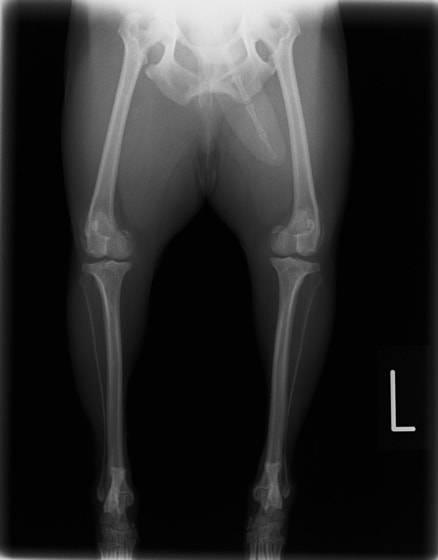

■ 症例22 ポメラニアン 1歳5か月 去勢雄

左後肢の挙上を主訴に来院した。整形学的検査、レントゲン検査より左右の膝蓋骨脱臼(左GradeⅡ〜Ⅲ、右Grade Ⅱ)を認めた。また、脛骨の前方引き出し試験の際に、引き出し兆候は認められないものの、疼痛が認められたため、前十字靭帯の損傷が疑われた。術中における、目視および関節内の操作によって、前十字靭帯の損傷や過伸展といった異常が認められなかったため、膝蓋骨脱臼の整復のみ実施した。手術手技は縫工筋及び内側広筋の解放、脛骨粗面の外側転位、滑車ブロック形造溝術、内外側関節包の縫縮を実施した。本症例は跛行もなく経過良好である。しかし、頸骨高平部の角度(TPA)が 右26.2°、左24.9°であり、解剖学的に前十字靭帯損傷のリスクが高いことから今後の経過に注意が必要である。